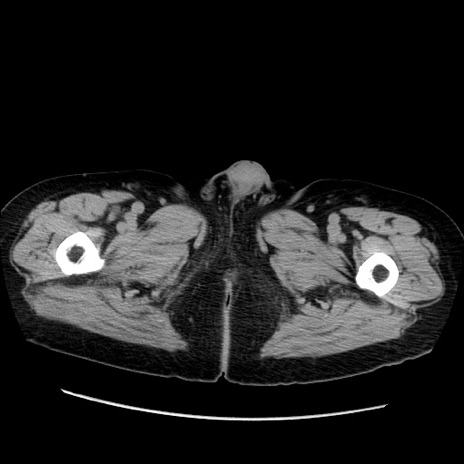

症例21(横断像)

【症例】70歳代男性

【主訴】腹痛

【現病歴】肝硬変・肝細胞癌にてかかりつけの方。約9時間前に食後より腹痛出現。症状が徐々に増悪し、嘔吐出現したため来院。

【既往歴】肝硬変、肝細胞癌(RFA、TACE後)

【身体所見】意識清明、表情苦悶様、BT 36℃、BP 129/78mmHg、P 88bpm、SpO2 97%(RA)、右上腹部から心窩部にかけて圧痛あり、反跳痛なし、筋性防御あり。

【データ】WBC 5800、CRP 0.16